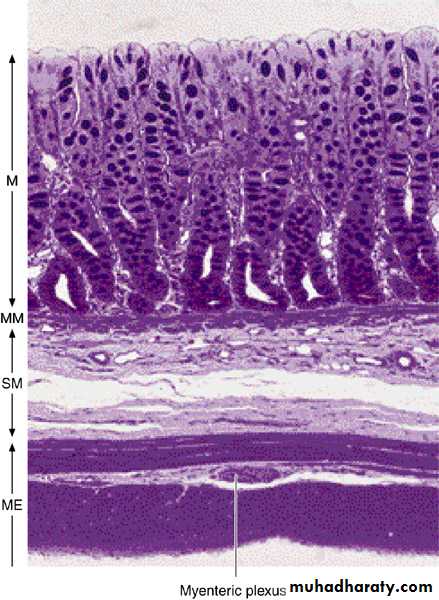

• Photomicrograph of a section of large intestine with its various layers. Note the absence of villi. M, mucosa; MM, muscularis mucosae; SM, submucosa; ME, muscularis externa. PT stain. Low magnification.

• Photomicrograph of a group of neurons (with large nuclei) and satellite cells (with small nuclei) constituting a component of the myenteric plexus between 2 smooth muscle layers. Note the red stained collagen fibers. Picrosirius-hematoxylin. Medium magnification.